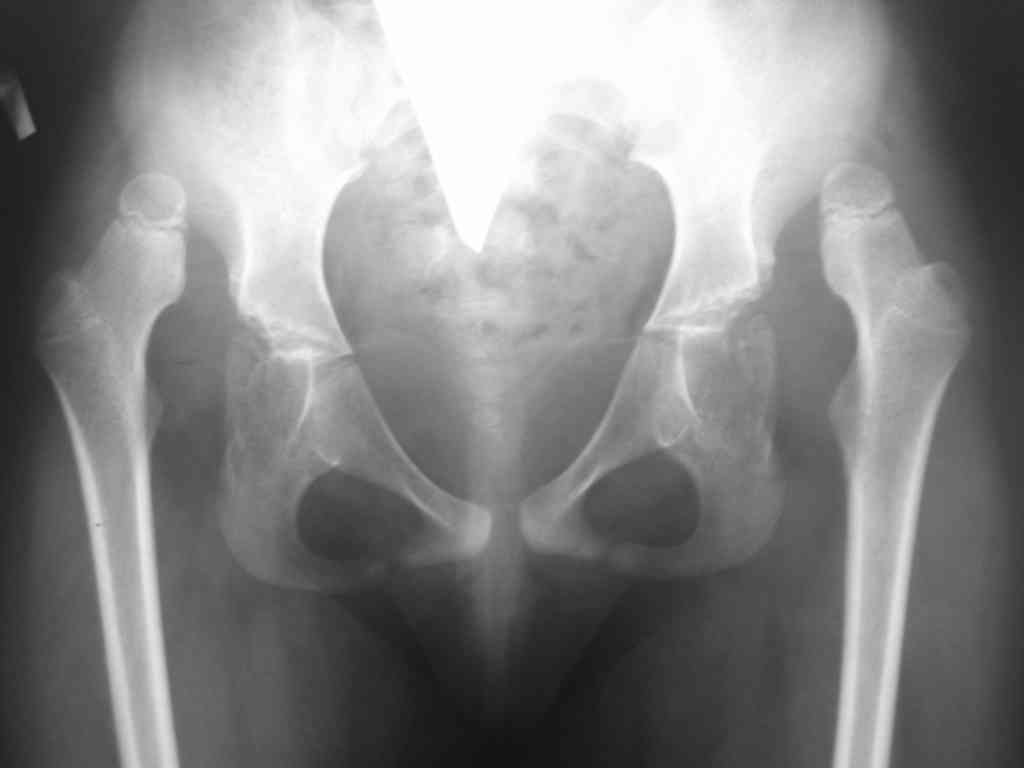

Обратились родители 7 летней девочки(1999г) с диагнозом:артрогрипоз, рецидивирующая двусторонняя косолапость, двусторонний высокий вывих бедер.

Наблюдается и лечится с 1.3 лет в детском ортопедическом институте имени Г.И.Турнера МЗ РФ Санкт-Петербург. В возрасте 1.3 года выполнены операцмм Штурма-Зацепиан по поводу двусторонней косолапости. По поводу рецидива косолапости 14.07.2004г операция Штурма-Зацепина справа + корригирующая лавсанопластика и 30.08.2004г операция Штурма-Зацепина слева + аппарат Илизарова; 29.09.2004г аппарат внешней фиксации удален на левой стопе+ корригирующая лавсанопластика левой стопы. В настоящее время больная передвигается в ортопедической обуви, рецидива косолапости нет. Родителей беспокоят состояние тазобедренных суставов-в институте им. Г.И.Турнера от вправления вывихов бедренных костей воздержались:обяснения докторов следующее: после вправления бедренных костей движения бедер может резко ухудшиться и больная не сможет себя обслуживать. Предлагают после завершения роста костей произвети тотальное эндопротезирование, а пока ждите.....И вот родители спрашивают.... да и я тоже.. как быть.. возможни ли низведение бедренных костей через, примерно 10-12 лет без последствий для нижних конечностей. А может кто из детских ортопедов и возмет девочку на лечение....?Заранее блогадарен.. Снимки тазобедреннх суставов прилагаются.